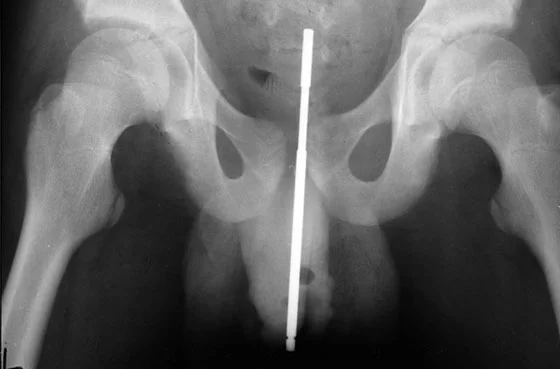

• “STUCK A NAIL IN URETHRA THEN IT MIGRATED UP INTO THE BLADDER”